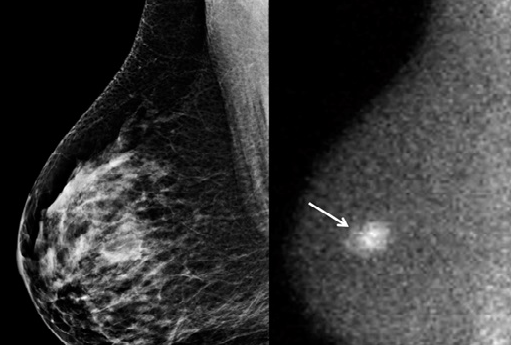

Breast imaging technique is used to detect cancer cells in breasts of women. This imaging technology helps in e early detection of breast cancer in women. The breast imaging techniques provides screening, diagnostic, surgical, and support services to a woman with breast cancer. Mammography, breast ultrasound, MRI and image-guided breast biopsy are some of the most common techniques for breast imaging.

The analysis concludes that continuing to innovate cost-effective technological solutions is the key to offsetting the high costs of breast cancer screening technologies. Examples include molecular breast imaging (MBI) systems, which Grand View Research notes are one-third the price of a typical MRI system. Molecular imaging systems show cellular function by tracing the activity of an injected radiopharmaceutical in the body. This can be employed as a cost-effective follow-up to a screening mammogram to try to reduce the number of false-positive findings requiring biopsies.